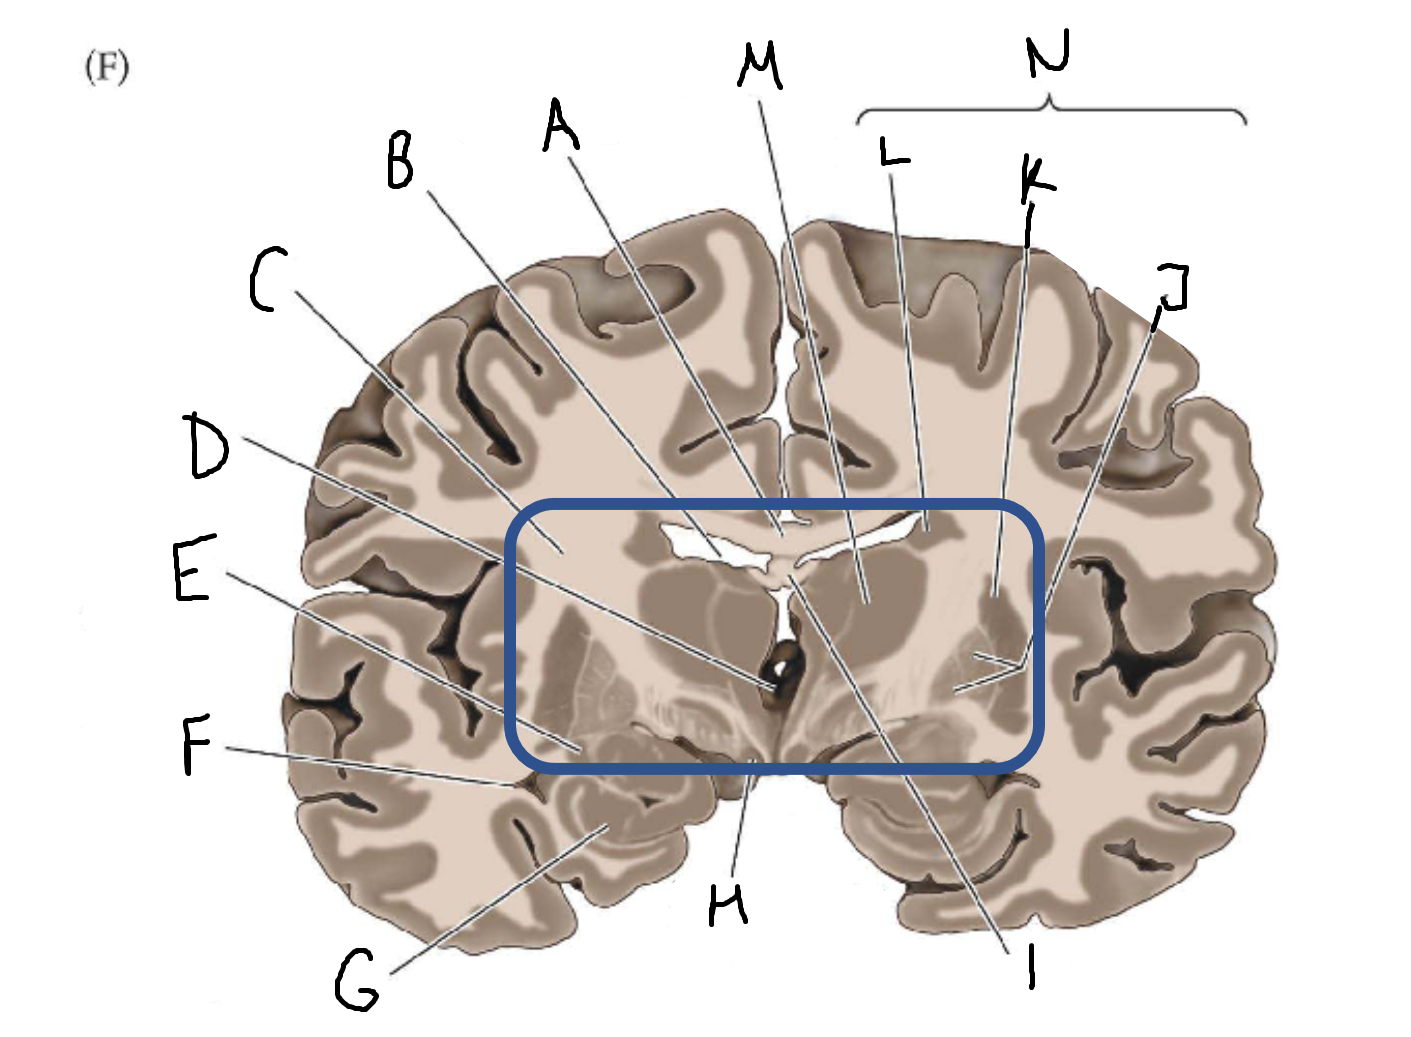

A

corpus callosum

B

lateral ventricle

C

internal capsule

D

third ventricle

E

tail of caudate nucleus

F

lateral ventricle

G

hippocampus

H

mammillary body

I

fornix

J

globus pallidus

K

putamen

L

caudate

M

thalamus

N

basal ganglia